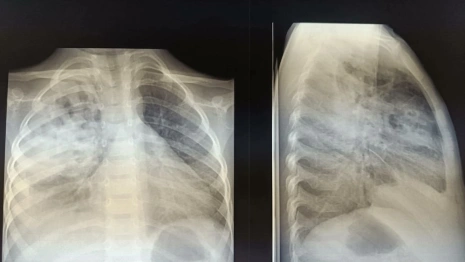

Малыш из Владимира заболел тяжелой формой деструктивной пневмонии с пневмотораксом. Его госпитализировали в ОДКБ со скоплением гноя и воздуха в плевральной полости, сообщила пресс-служба медучреждения во вторник, 26 декабря.

Ребенку потребовалась помощь хирурга. Врач выполнил дренирование плевральной полости и подобрал антибактериальную терапию. Также малышу назначили физиотерапию.